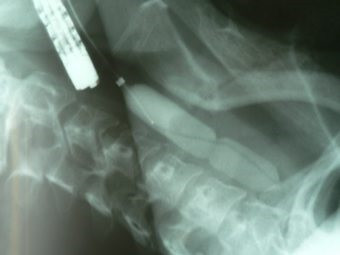

Dilatación esofágica con balón

Envíado por Dr. Carlos Miguel Zavaleta Consuegra